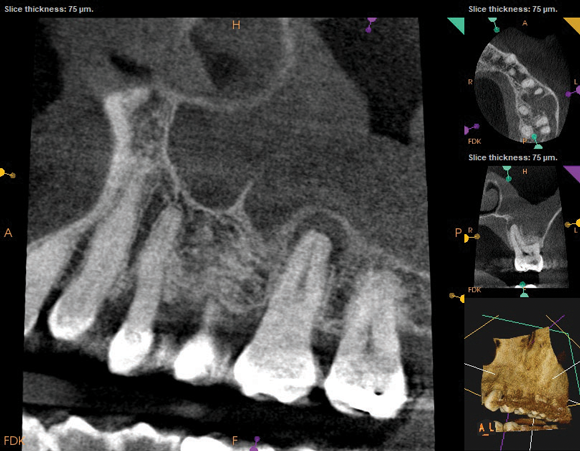

The diagnosis for tooth No. 14 was pulpal necrosis with asymptomatic apical periodontitis. NSRCT was completed (Figure 9), followed by full-coverage restorative care performed by the general dentist. A 3-month follow-up revealed resolution of prior sinus symptoms, normal clinical findings, and healing radiographic pathology, including periapical pathology and associated maxillary sinus mucositis (Figure 10 and Figure 11).

Fig 10. CBCT imaging at 3-month follow-up showing signs of healing and decrease in maxillary sinus mucositis. Fig 10: Sagittal view, buccal roots No. 14. Fig 11: Sagittal view, palatal root No. 14.

Fig 11. CBCT imaging at 3-month follow-up showing signs of healing and decrease in maxillary sinus mucositis. Fig 10: Sagittal view, buccal roots No. 14. Fig 11: Sagittal view, palatal root No. 14.